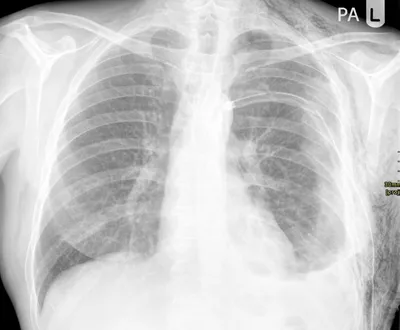

Avascular Necrosis right femoral head

XRAYAVNAvascular Necrosis+1

4/23/2026